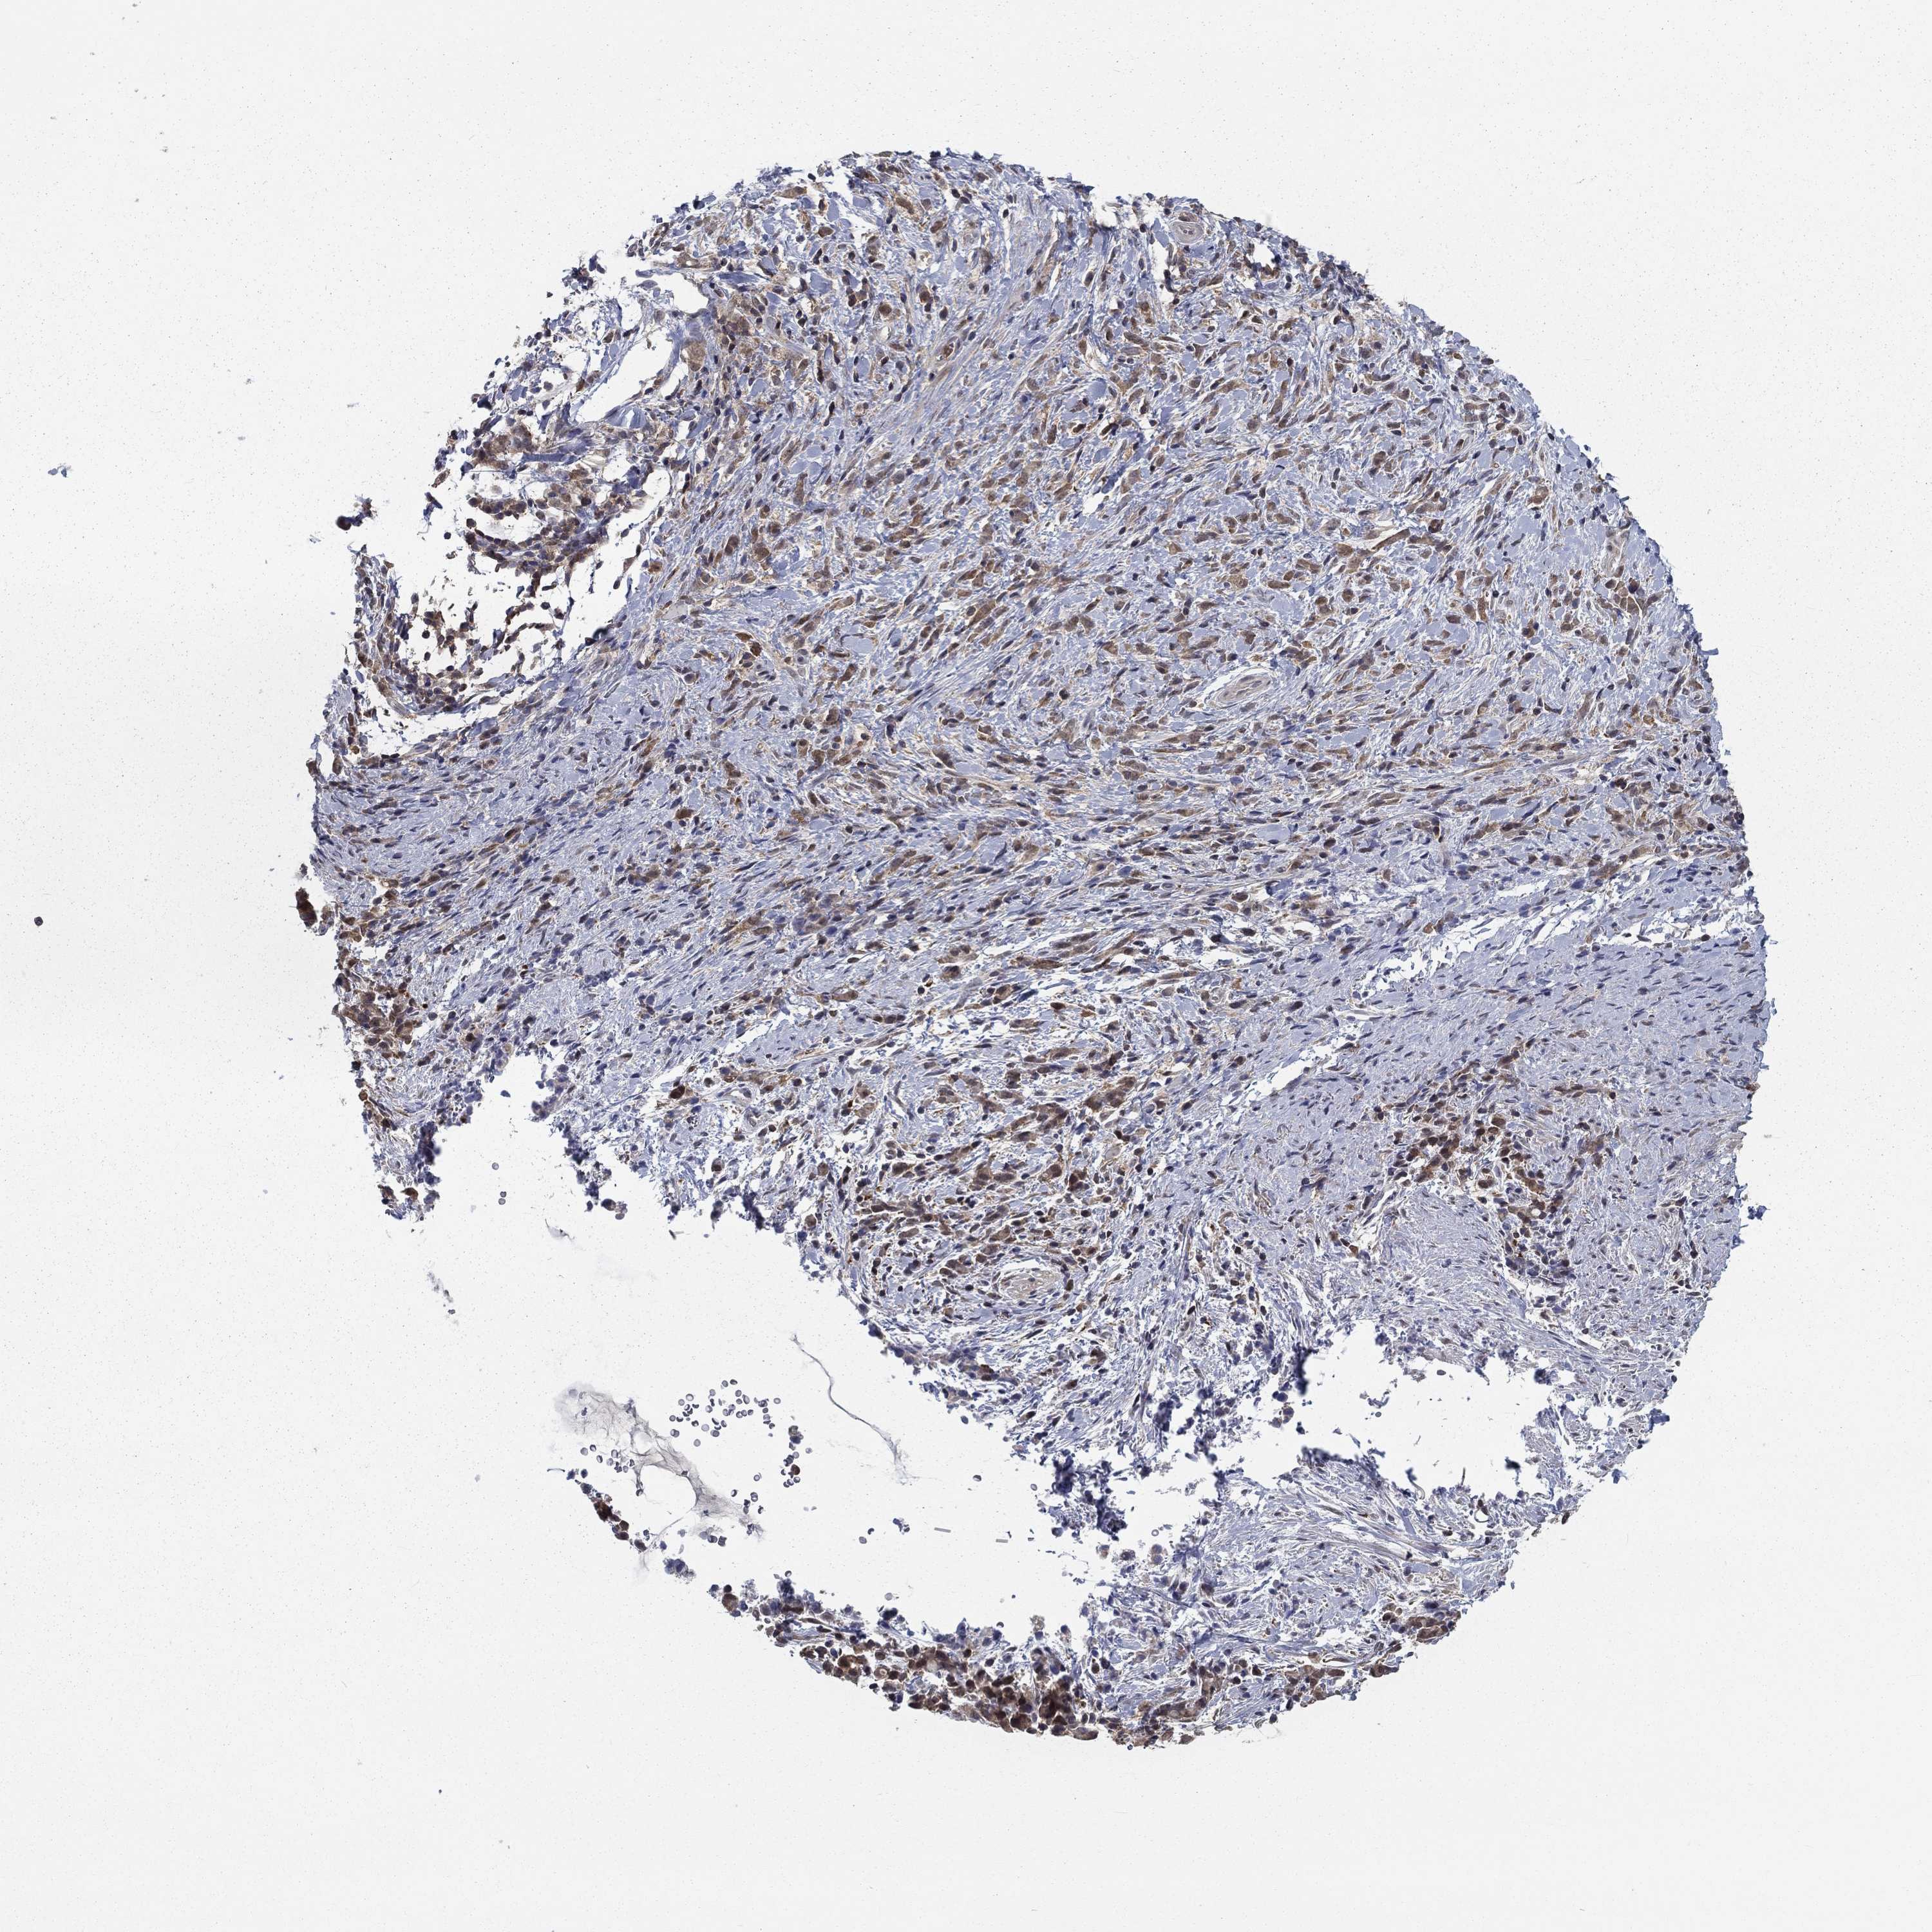

STOMACH CANCER - Protein expressioni

A mouse-over function shows sample information and annotation data. Click on an image to view it in a full screen mode. Samples can be filtered based on level of antibody staining by selecting one or several of the following categories: high, medium, low and not detected. The assay and annotation is described here.

Note that samples used for immunohistochemistry by the Human Protein Atlas do not correspond to samples in the TCGA dataset.

Antibody stainingi

Antibody staining in the annotated cell types in the current human tissue is reported as not detected, low, medium, or high, based on conventional immunohistochemistry profiling in selected tissues. This score is based on the combination of the staining intensity and fraction of stained cells.

Each image is clickable and will lead to virtual microscopy that enables deeper exploration of all samples and also displays staining intensity scores, fraction scores and subcellular localization as well as patient and tissue information for each sample.

Antibody HPA036999

Antibody HPA041289

Staining

High

Medium

Low

Not detected

Intensity

Strong

Moderate

Weak

Negative

Quantity

>75%

75%-25%

<25%

None

Location

Nuclear

Cytoplasmic/membranous

Cytoplasmic/membranous,nuclear

Adenocarcinoma, NOS

Adenocarcinoma, High grade